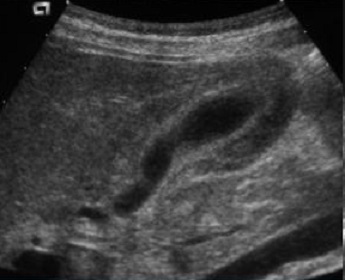

Echographie et cliche de face ASP : Image

echographique de hepatite aigue est image de hepatomegalie ,

parenchyme hypoechogene , voie biliaire est fine ,

epaissisement de paroi de la vesicule biliaire . Image

de "starry night " de la parenchyme du foie ou adenopathie

hillaire parfois en se voyait . Cliche de ASP de face est

image de hepatomegalie .

Aspect echographique de

hepatite aigue : Image de hepatomegalie ,

hypoechogene du foie et image de " starry

night " du foie . Ce signe est caracteristique par

accentualisation de la venule portale et la

diminution de echoriche des cellule oedemateuse de

la parenchyme du foie |

Image le plus souvent en

voyait dans hepatite aigue est image de

epaissisement oedemateuse de la vesicule biliaire .

Plus de > 3mm de epais |